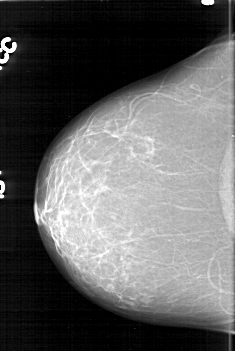

D_4195_1.LEFT_MLO

LEFT_MLO LINES 6466 PIXELS_PER_LINE 4006 BITS_PER_PIXEL 12 RESOLUTION 43.5 OVERLAY